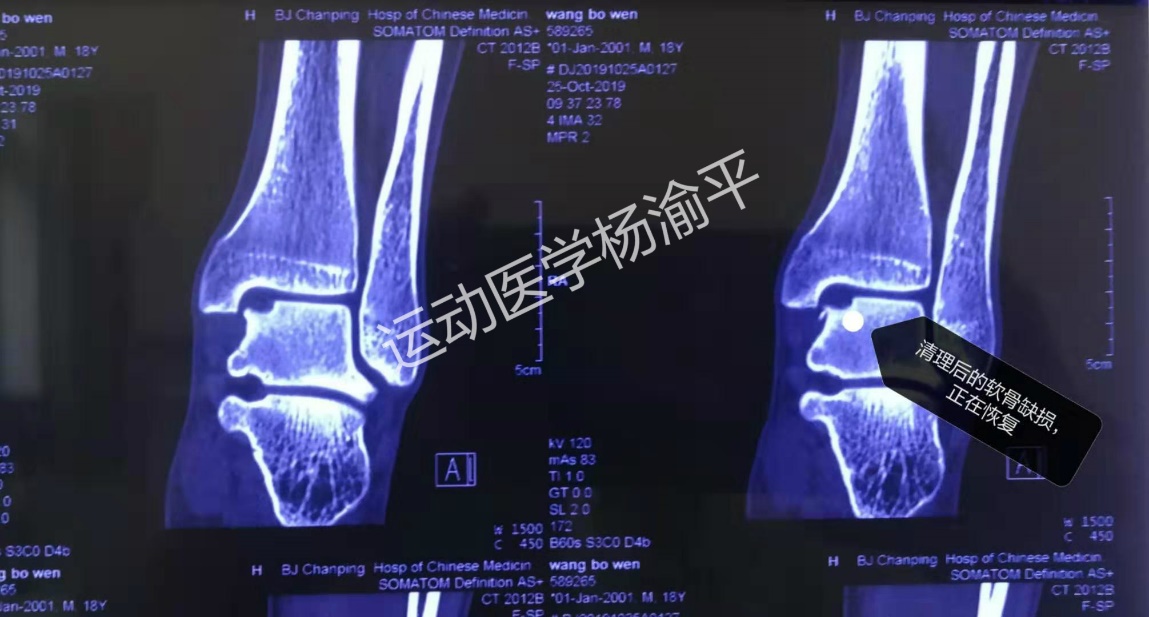

进行手术清理后,正在恢复的软骨缺损

其实我们就是给他做了关节镜下的简单清理,而没有做骨软骨移植或是微骨折手术。 之所以要介绍这个案例,就是想告诉大家:

第二,其实从我个人的经验来看,绝大多数的(骨)骨软骨损伤经过关节镜下清理后,恢复效果都比较满意很好。就像今天介绍的这个案例一样,患者术后四周就能正常走路,能满足一般的正常生活需求。并不一定需要做很复杂的手术,我们完全可以用最小的代价获得最大的收益。